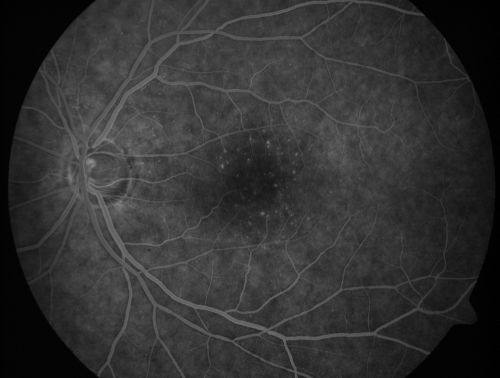

Juxtafoveal Telangiectasis - After Hemorrhage Absorbed Right Eye with Avastin Injections

73-year-old woman has juxtafoveal retinal telangiectasis in both eyes.  The right eye has stage 5 disease.  Her last Avastin treatment in the right eye was in 6 months ago.  The right eye has been the worst of her two eyes for years.

VISUAL ACUITY: Vision OD is 20/200, OS is 20/50.